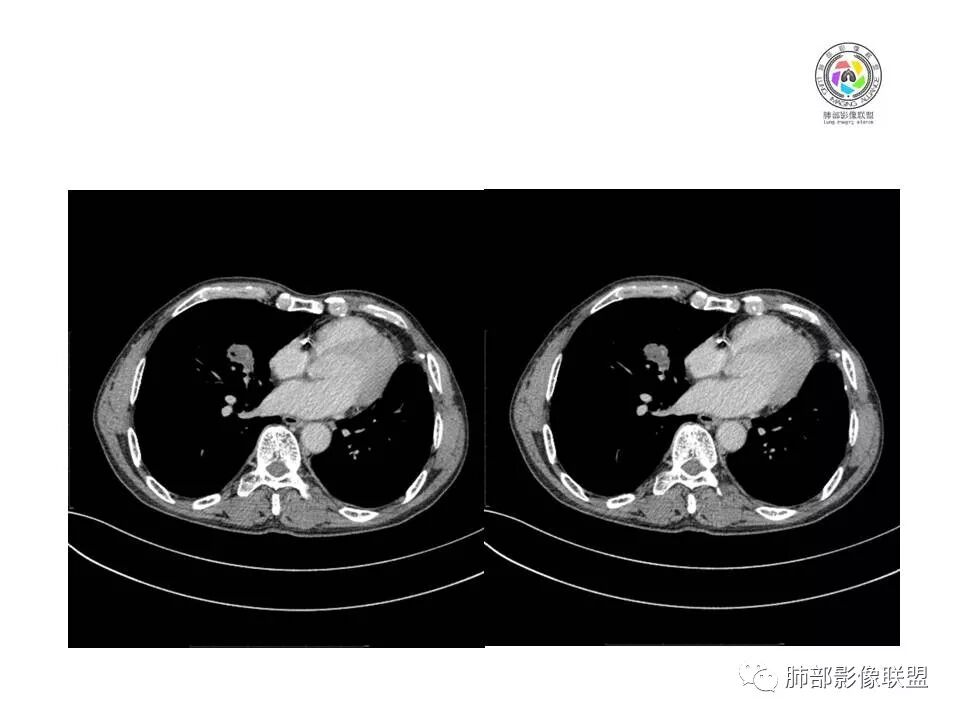

患者老年男性,间断咳嗽、咳痰伴痰中带血2个半月就诊,胸CT:右肺中叶内侧段占位性病变,病变可见分叶,周围可见结节影。病灶内可见厚壁空洞,洞壁光滑,未见洞壁结节,右肺中叶内侧段近肺门处支气管壁增厚。诊断:考虑结核,鉴别:肺癌,建议痰找抗酸杆菌、支气管镜检查

右肺中叶内侧段实性病灶,病变可见深分叶,棘突,毛刺,周围多发结节影。病灶内可见厚壁空洞,内壁光滑,未见壁结节,增强轻度强化,右中叶内侧段支气管壁增厚。诊断:肉芽肿性病变,结核?隐球?鉴别:肺癌

LCNEC最常见的影像特征包括:(1)肿块发生部位:周围型肺癌为主,少数发生于肺中央。(2)肿块大小及形态。因肿瘤细胞生长迅速常形成较大肿块,因此其体积一般较大,直径常在3~10cm范围内,病灶常为不规则形软组织肿块。(3)肿块边界。多数学者报道大多数肿块边界清晰,边缘呈分叶状,毛刺征及“胸膜凹陷征”少见,认为与该病对周围组织浸润较轻及较少产生纤维瘢痕组织牵拉有关联。(4)肿块密度、强化特点及代谢情况。据文献报道,该类肿瘤因体积较大CT上常见软组织肿块,且多数密度不均匀,内见囊变坏死区,增强后呈轻或中度不均匀强化(可见强化者占75.7%),认为其强化特点与其内部肉眼可见坏死灶和肿瘤较大直径有关。(5)伴随症状及远处转移。该病恶性程度高,侵袭性强,常侵犯邻近结构,如胸膜、心包、邻近骨质或纵隔内组织等,易出现纵隔淋巴结转移,部分发生肺内及远处转移,少数早期可出现广泛远处转移。

LCNEC患者空洞、钙化、阻塞性肺炎、肺不张、积液这些CT特征较少见,少见支气管充气征。